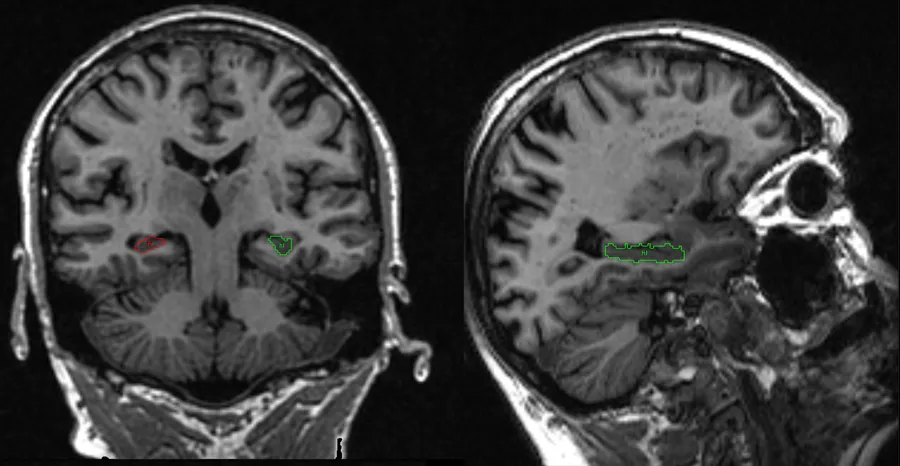

Manual delineation of hippocampus in community-dwelling non-demented adults. Image When analyzing specific parts of the brain (here a region called the hippocampus), it is often necessary to manually delineate these regions. The manual tracing here illustrates hippocampus. Hippocampus is important for memory. Reduction of hippocampal volume is associated with Alzheimer’s disease, multiple sclerosis, schizophrenia, & age-related cognitive decline. We assess changes in hippocampal volume & integrity in a large sample of community-dwelling non-demented ageing adults at 73, 76 & 79 years of age. Created by: Devasuda Anblagan, Ian Deary, Joanna Wardlaw Edinburgh DataShare for access to files Relevant links Professor Joanna Wardlaw Professor Ian Deary Devasuda Anblagan Brain & nervous system Dementia Multiple sclerosis This article was published on 2024-08-22